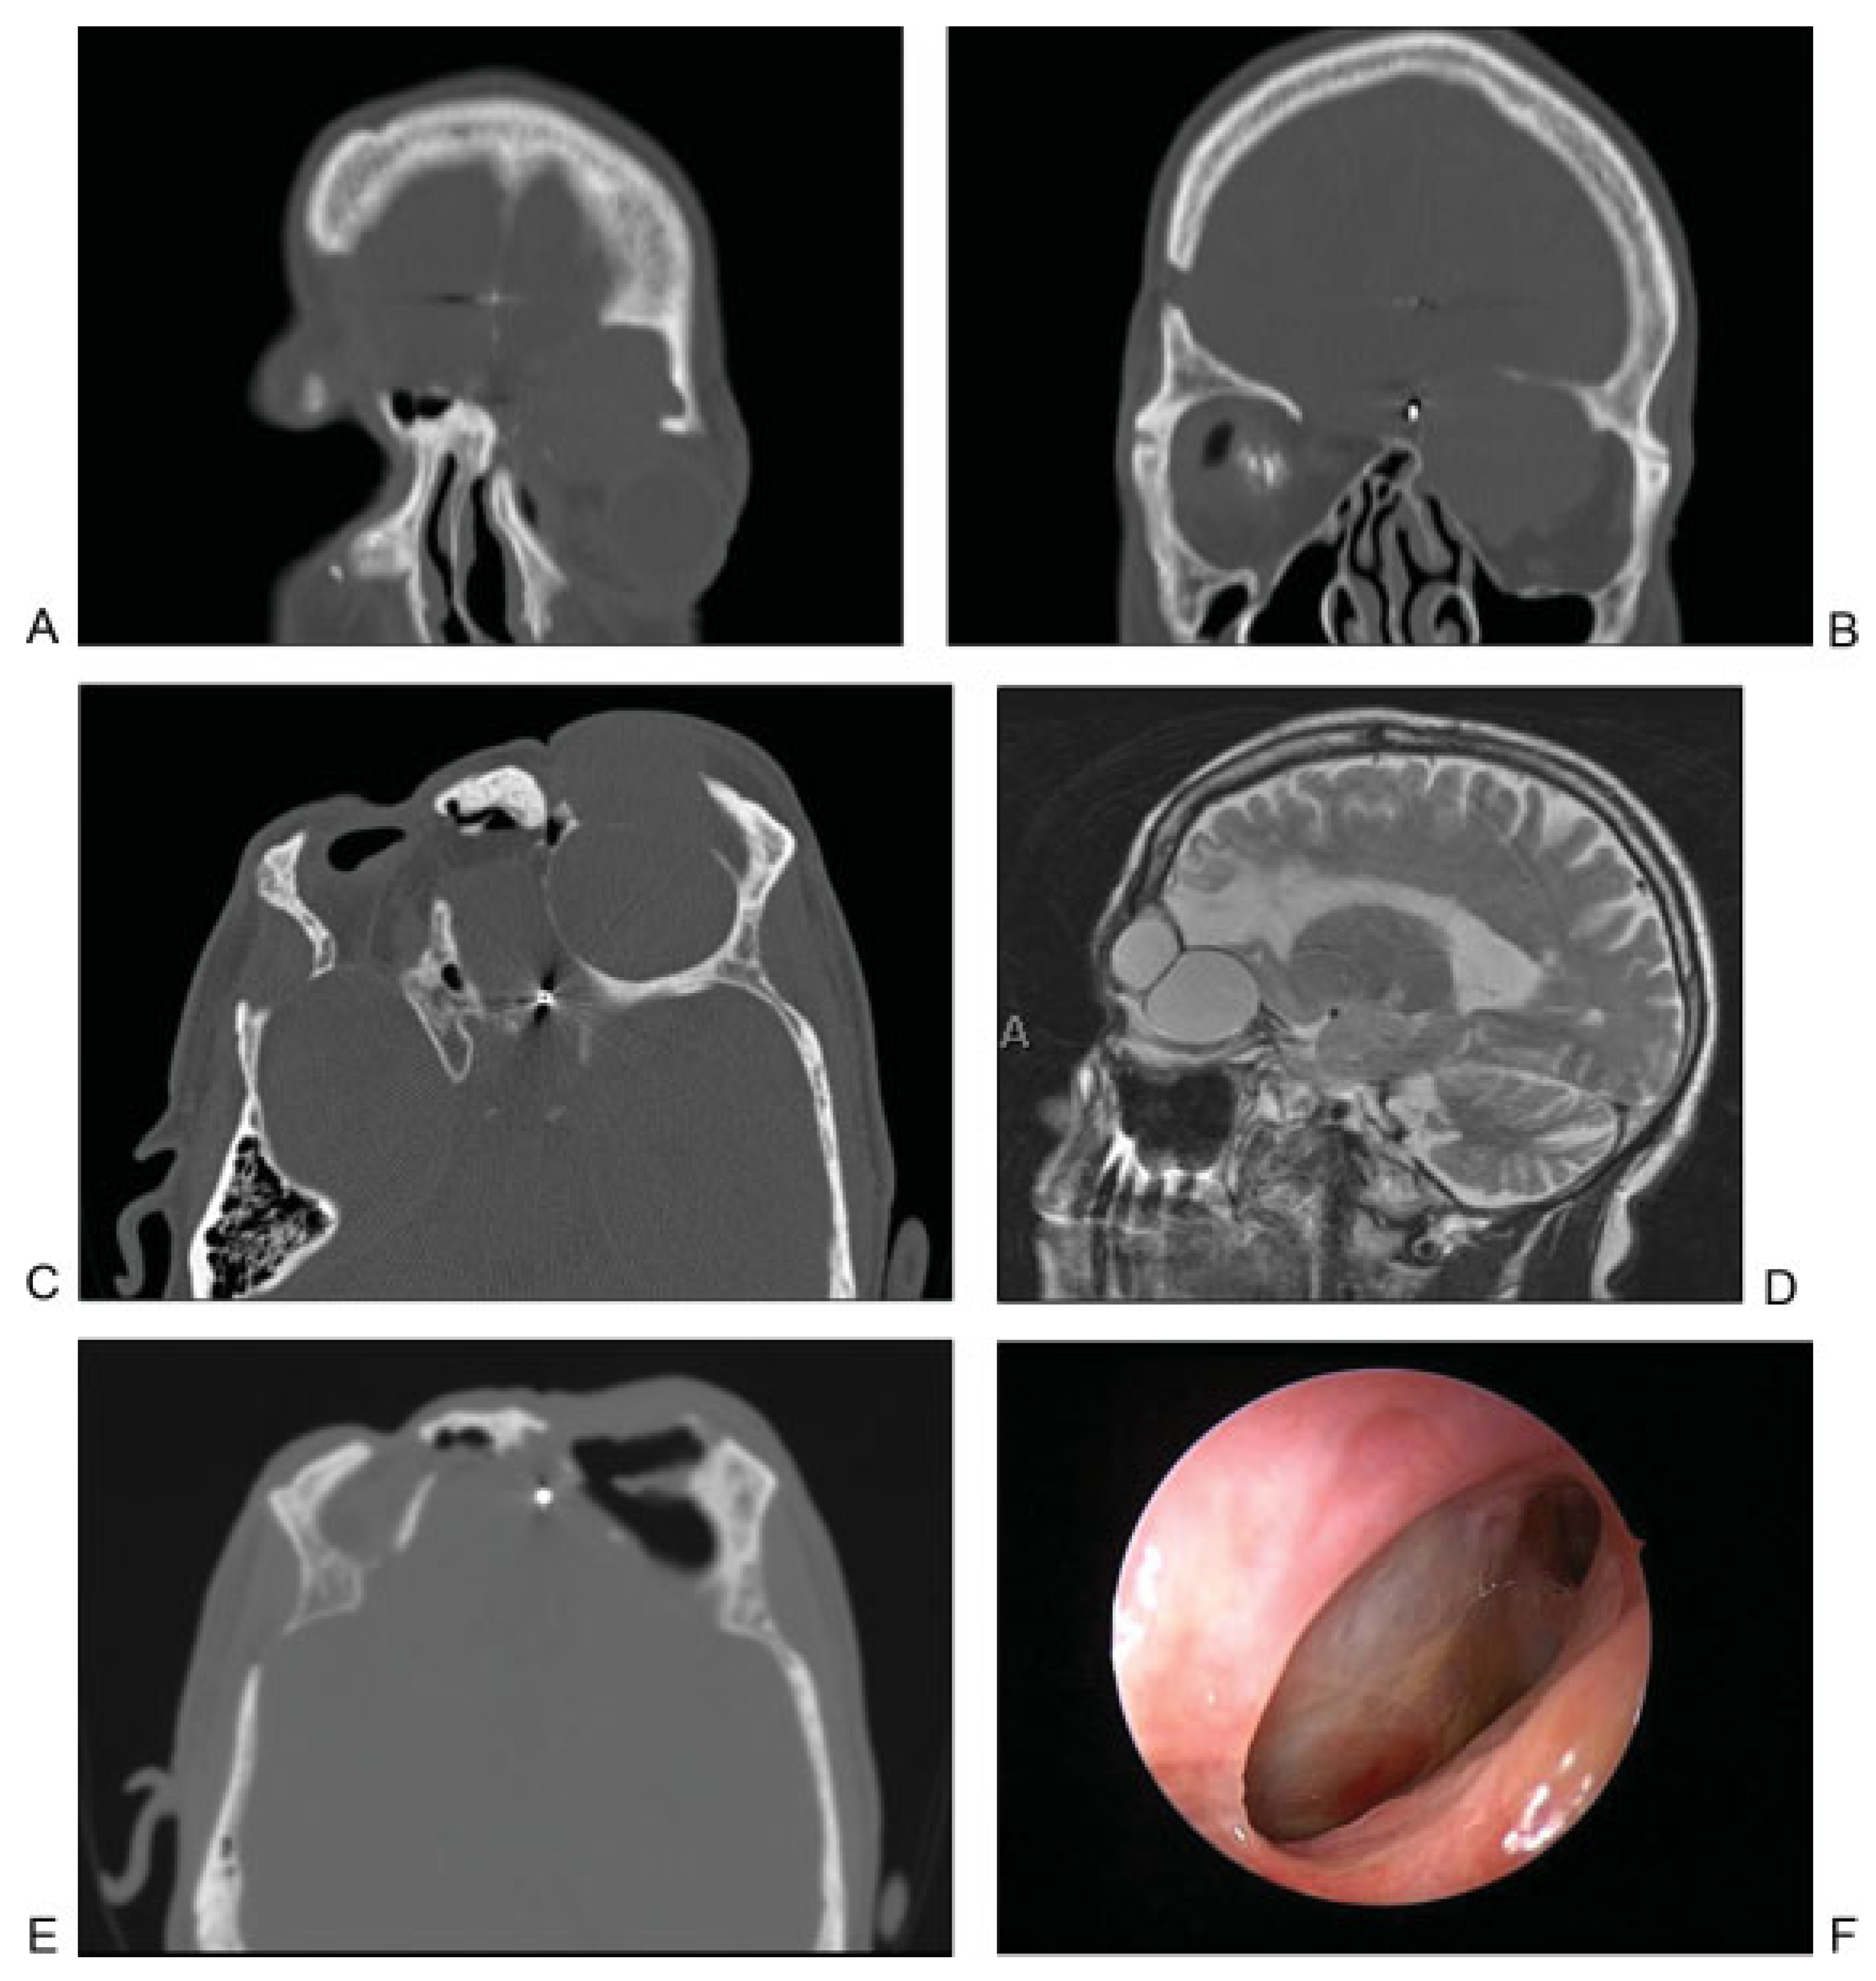

Figure 5.

(A) Coronal computed tomographic (CT) image showing mucocele that developed in a delayed fashion after extensive frontal sinus trauma and previous cranialization. Image shows mucocele with orbital and intracranial involvement. (B) Coronal CT image showing orbital mucocele. (C) Axial CT image demonstrating two separate mucoceles involving the left frontal and orbital regions. (D) Sagittal MRI demonstrating two distinct mucoceles. (E) Postoperative axial CT image demonstrating aeration of both mucocele cavities after endoscopic marsupialization. (F) Postoperative endoscopic view of the outflow tract of the two mucoceles after complete healing.